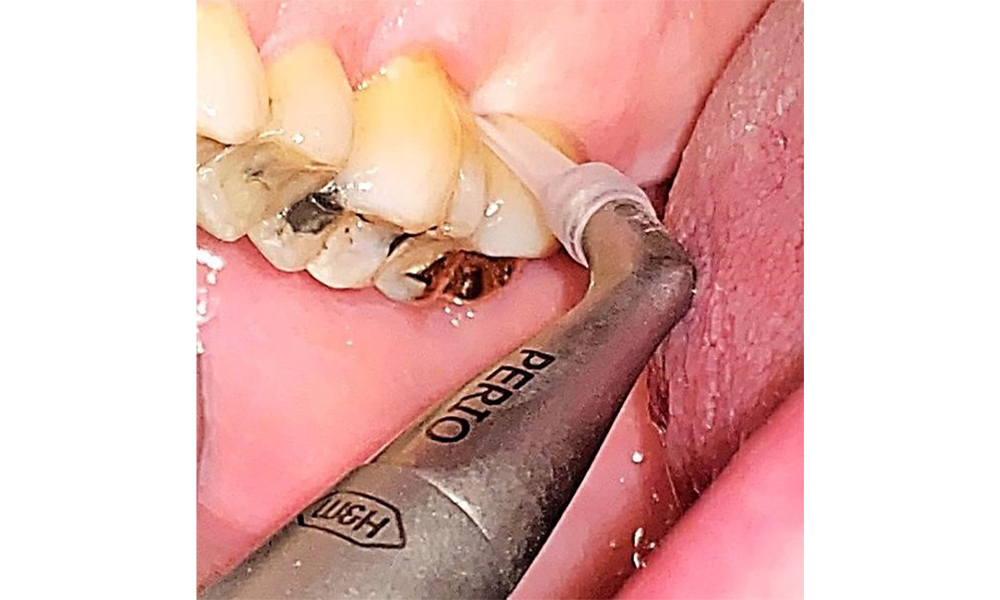

Използване на ултразвуков накрайник за отстраняване на твърда минерализирана плака (скалер Proxeo Ultra с перио накрайник, W&H).

Фиг. 9: Използване на ултразвуков накрайник за отстраняване на твърда минерализирана плака (скалер Proxeo Ultra с перио накрайник, W&H). © д-р Р. Крапф

Няма ограничения по отношение на избора на методи за измерване. Редовната супрагингивална и субгингивална инструментация е от съществено значение за предотвратяване на прогресията на заболяването поради вече съществуващия пародонтит и високия риск от рецидив. От общомедицинска гледна точка няма ограничения върху избора на инструменти за механично отстраняване на биофилм и отстраняването трябва да се извършва според нуждите. Твърдата и минерализирана плака, като зъбен камък и конкременти, трябва да се отстранява с помощта на ръчни инструменти или ултразвукови скалери (фиг. 9) (8, 9).